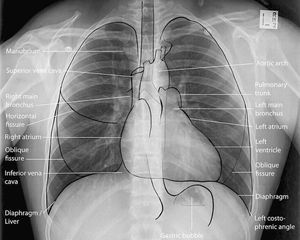

Chest X-Ray shows the mediastinal structures

The trachea is shown here where it is divided into right and left main bronchus.